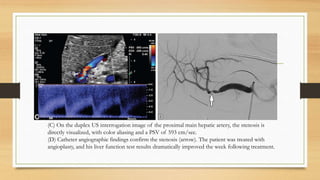

(C) On the duplex US interrogation image of the proximal main hepatic artery, the stenosis is

directly visualized, with color aliasing and a PSV of 593 cm/sec.

(D) Catheter angiographic findings confirm the stenosis (arrow). The patient was treated with

angioplasty, and his liver function test results dramatically improved the week following treatment.

Early hepatic artery thrombosis with hepatic infarct in a 44-year-old man with markedly elevated

liver function test results at routine follow-up 2 weeks after transplant.

(A) Duplex Doppler US image of the region of the hepatic artery at the porta hepatis shows

trace remnant flow with poor arterial pulsatility, suggestive of impending hepatic artery

thrombosis. A strong arterial tracing was seen in the celiac axis, but the hepatic artery origin

could not be found (not shown).

(B) Transverse gray-scale US image of the left hepatic lobe shows a peripheral wedge-shaped

hypoechoic heterogeneous area (arrow) consistent with hepatic infarct.